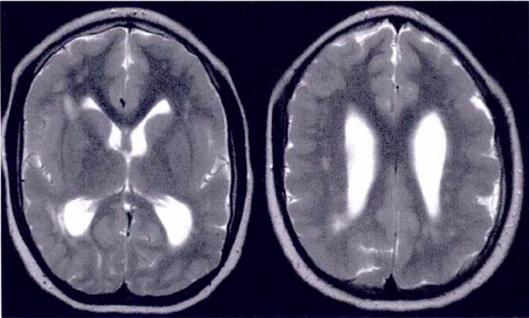

Lisencefalia. RM axial com escassez de sulcos/giros (direita) comparado com o padrão normal (esquerda).